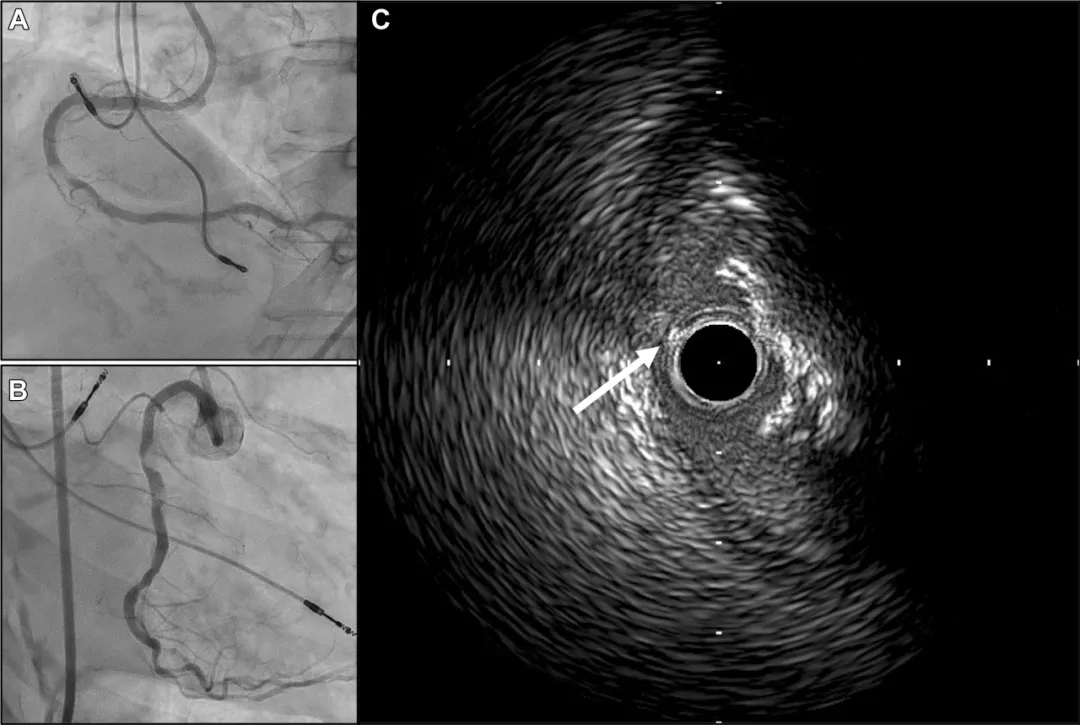

首次手术一周后,对RCA进行了再次介入治疗。经8F指引导管将工作导丝(SION blue,ASAHI INTECC)送入残余真腔。造影和IVUS显示偏心性钙化结节位于心室侧,且导丝偏向不利于旋磨术或轨道旋磨术(图2)。此外,患者RCA数年前已使用1.75mm旋磨头接受过旋磨治疗。虽然定向冠状动脉斑块旋切术可减少钙化结节体积,但该导管体积较大,难以通过严重的钙化狭窄病变。

图2 二次手术冠状动脉造影及IVUS图像

(A)右冠状动脉中段仍存在严重狭窄。

(B)病变位于心室侧。

(C)残余真腔内的导丝位于钙化结节对侧,该导丝偏向不利于旋磨术及轨道旋磨术(白箭头指示导丝)。